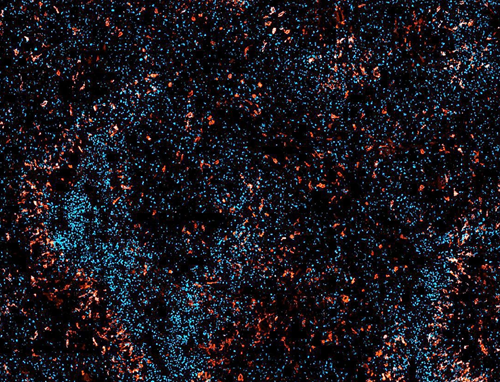

Leila Akkari aims to gain a better understanding of how immune cells influence tumour development. Furthermore, she wants to develop the right research tools to translate this knowledge into therapeutic advances.